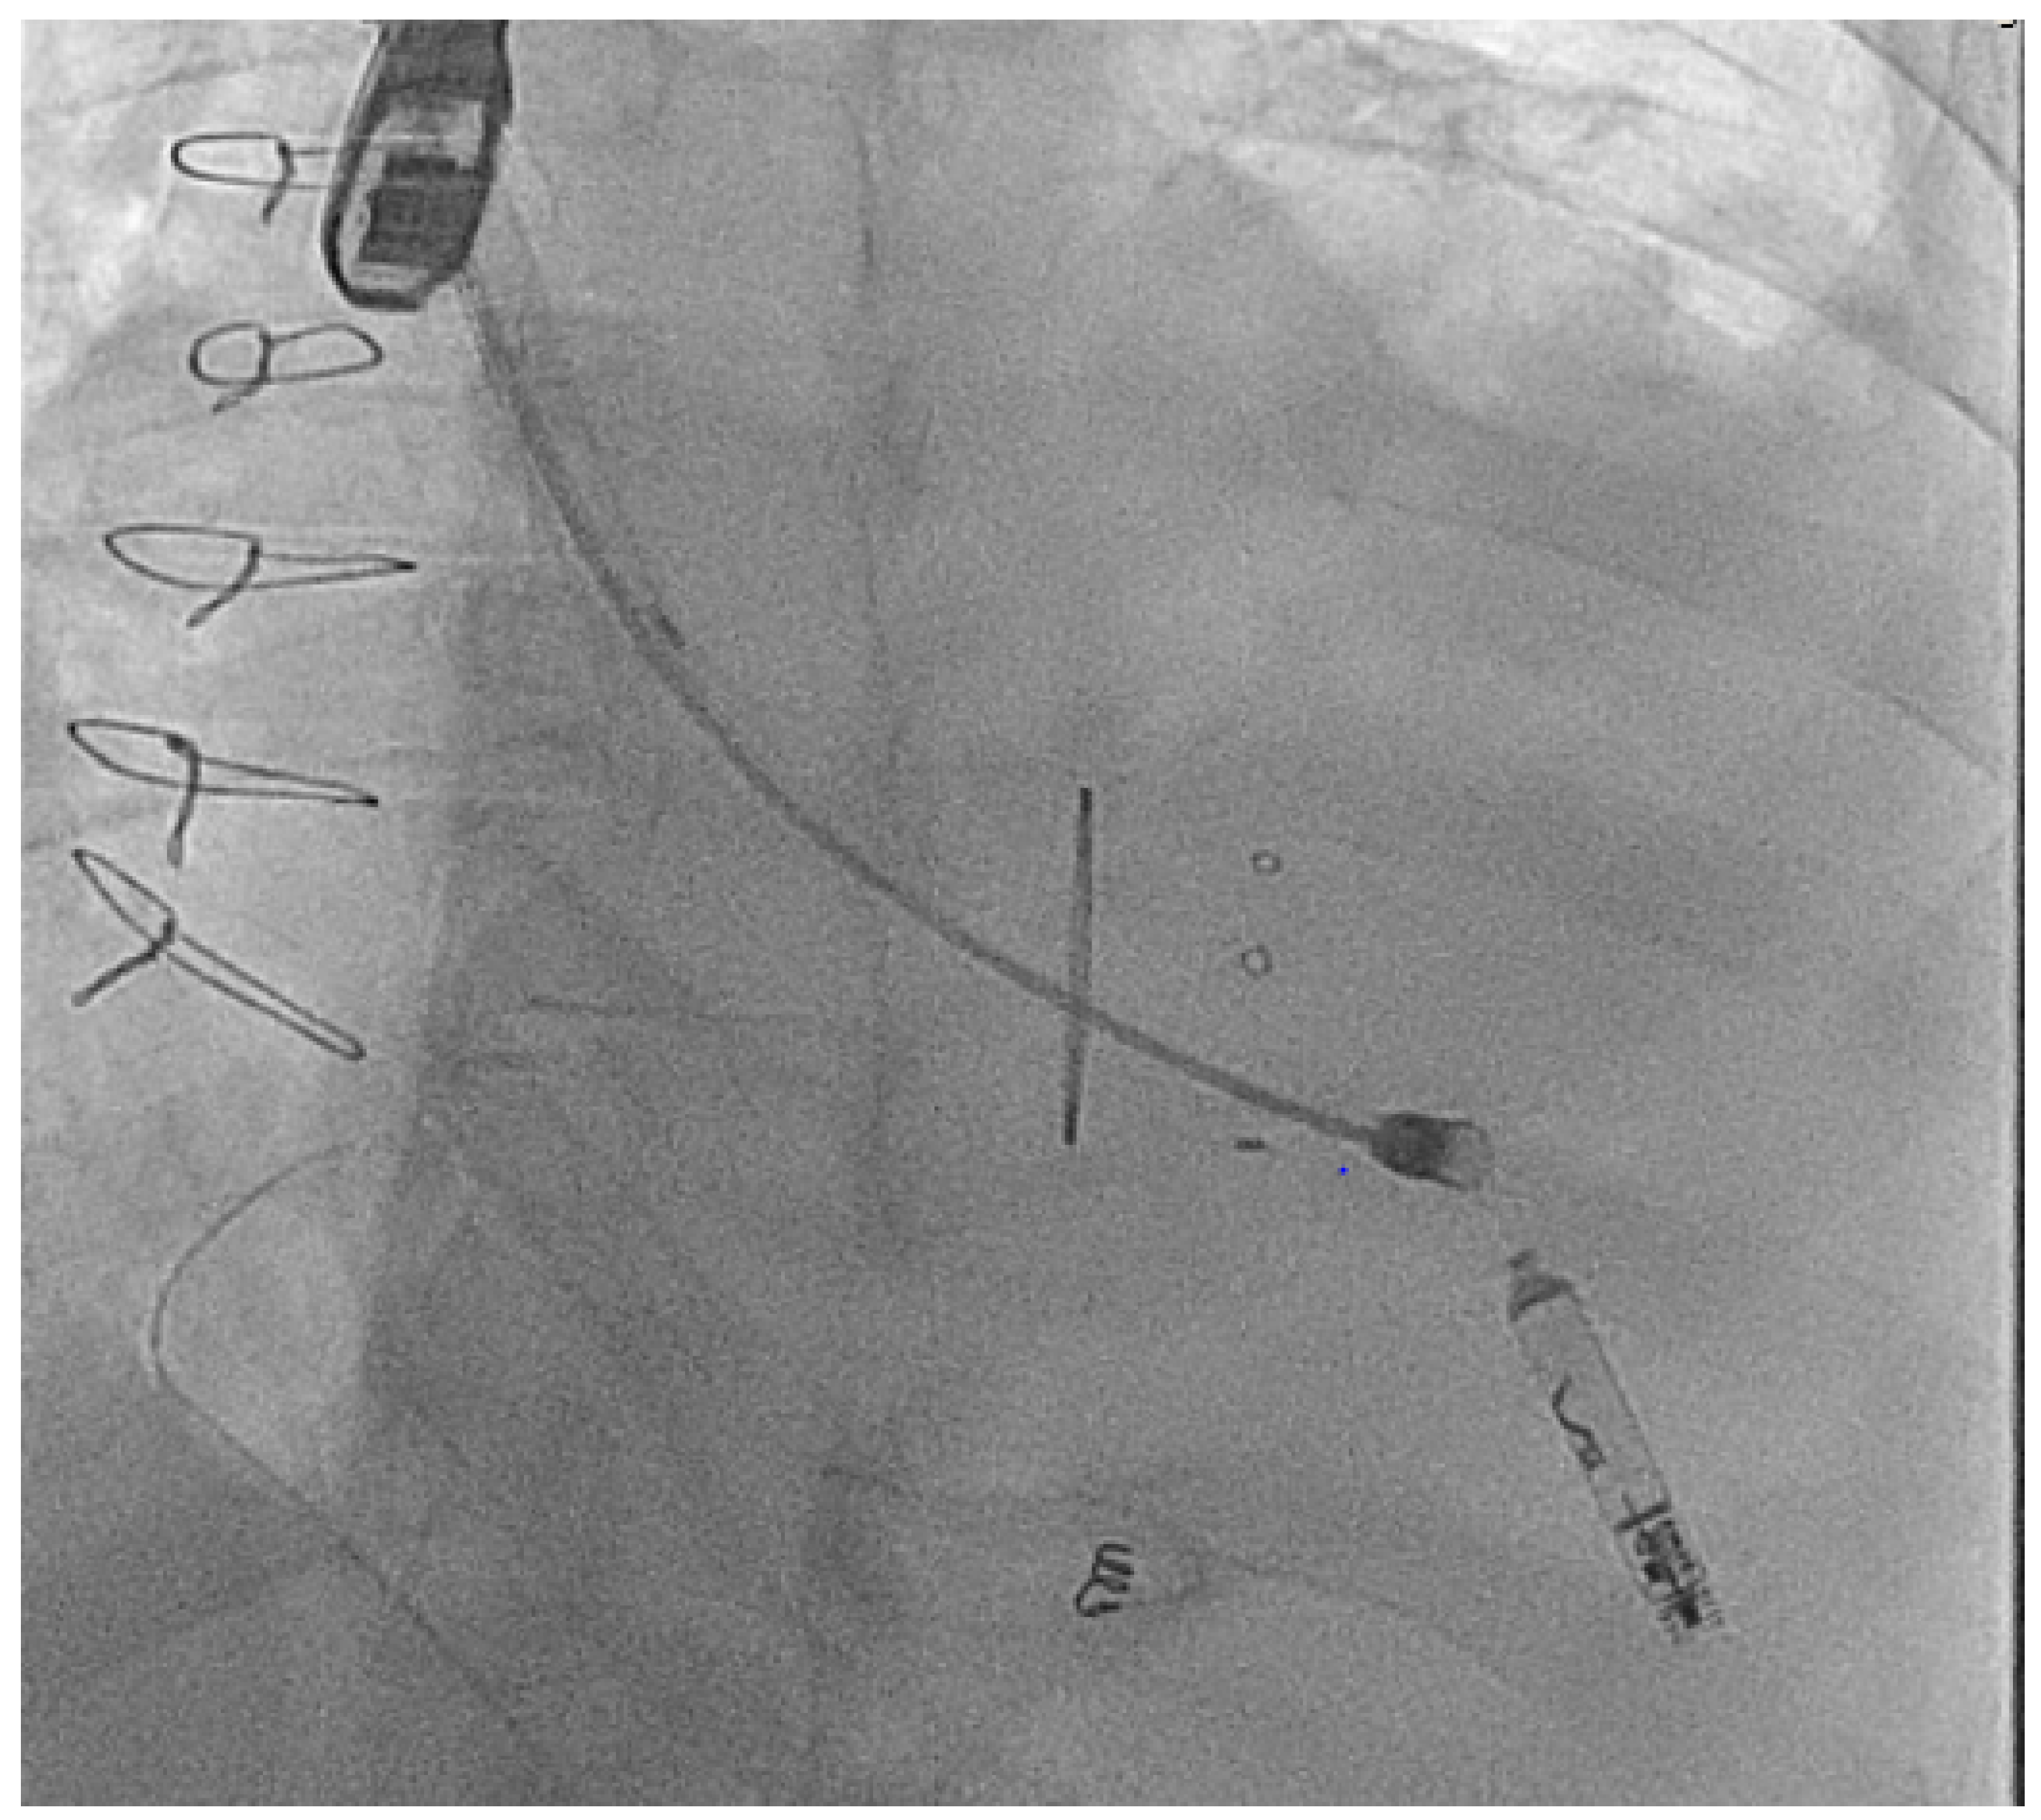

- Hayle, P.; Altayeb, F.; Hale, A.; Rao, A.; Ashrafi, R. Case report demonstrating novel approaches for leadless pacemaker implantation in the single ventricle heart. Eur. Heart J. Case Rep. 2025, 9, ytaf146. [Google Scholar] [CrossRef]

- Goulden, C.J.; Khanra, D.; Llewellyn, J.; Rao, A.; Evans, A.; Ashrafi, R. Novel approaches for leadless pacemaker implantation in the extra-cardiac Fontan cohort: Options to avoid leaded systems or epicardial pacing. J. Cardiovasc. Electrophysiol. 2023, 34, 2386–2392. [Google Scholar] [CrossRef]